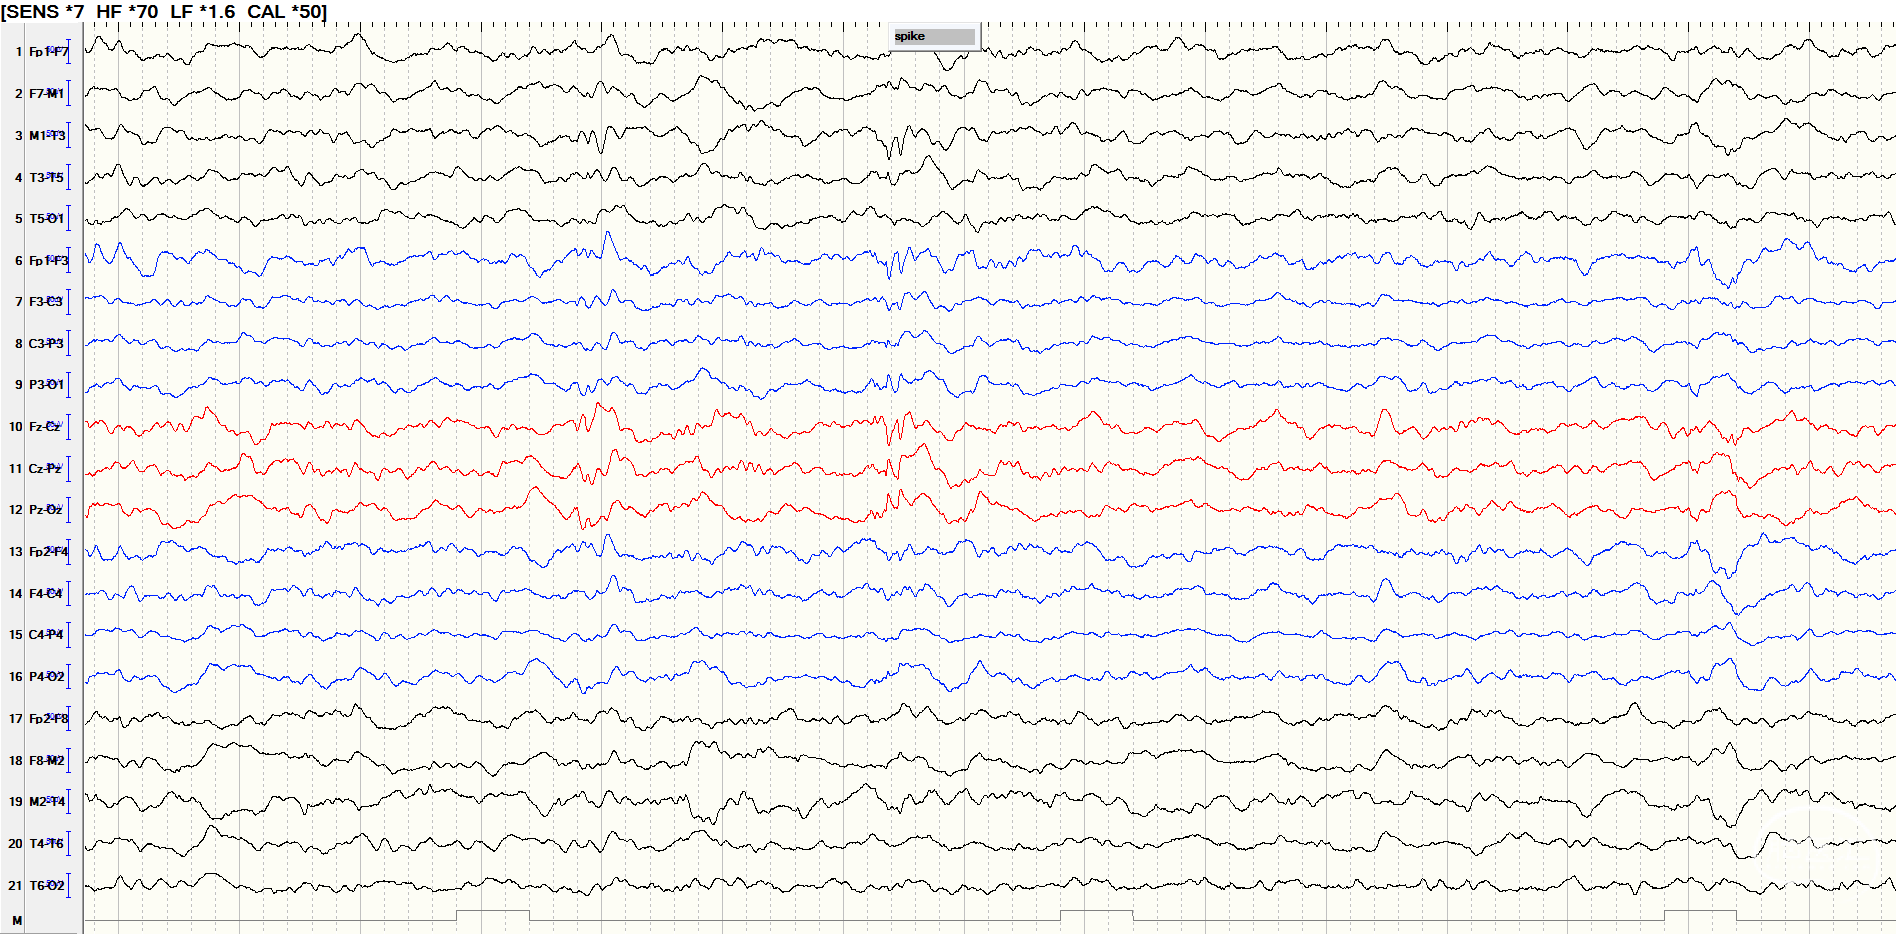

后转求至我院,详细询问病史并完善查体后发现患者脐下、右侧股外侧2*3cm色素脱失斑(图1)。完善脑电图检查提示间歇期放电脑区性,左后头著(图2),4天共监测到3次临床发作,表现为先兆(右肩重压过电感)→强直发作(累及右上肢)→阵挛发作(右上肢远端),同步脑电图示弥漫性电压低减,无侧向性(图3)。头颅MRI提示颅内多发异常信号(图4)。头颅CT提示颅内有钙化灶(图5)。头颅PET见左侧楔前叶低代谢(图6)。

图2.间歇期放电脑区性,脑区性,左后头著。

![]()